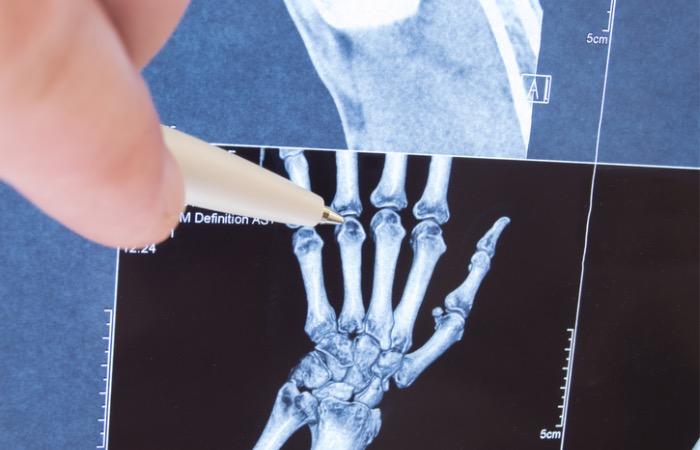

Pour étudier l’évolution de la croissance osseuse, les chercheurs ont utilisé les radiographies des poignets et des mains de plus de 1000 enfants nés entre 1915 et 2006. Ils ont prêté attention à la fusion épiphyse qui correspond au moment où l’os a terminé de grandir et où la calcification osseuse est achevée.

Ils ont constaté que les os des enfants nés dans les années 1990 terminent la fusion épiphyse plus tôt en comparaison à ceux nés dans les années 1930. Pour les fillettes, cela arrive en moyenne dix mois plus tôt et sept mois pour les garçons. Ces différences ne sont pas surprenantes, car depuis de nombreuses années, il est admis que les filles terminent cette croissance osseuse plus tôt que les garçons.